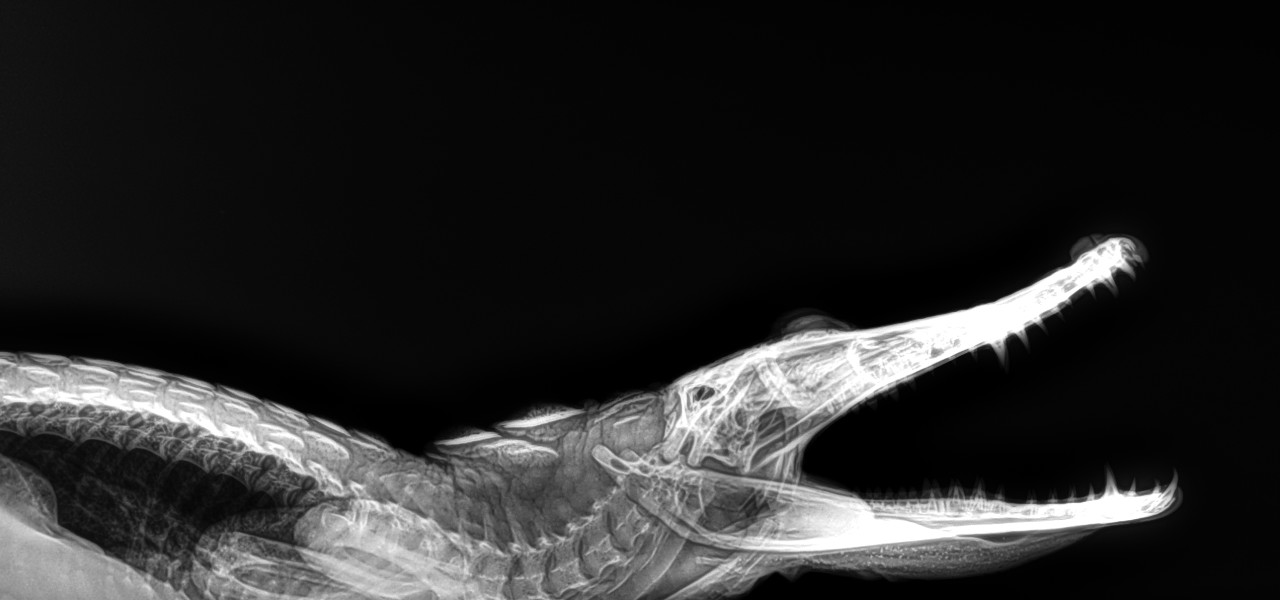

Animales

- Animales exóticos

Somos una empresa con más de 10 años de experiencia en radiología digital directa, dedicada a apoyar a médicos humanos, médicos veterinarios, antropólogos, biólogos, geólogos, paleontólogos, restauradores, anticuarios, peritos en obras de arte, que requieran realizar placas radiográficas digitales directas, in situ para analizar y en su caso, confirmar el diagnóstico o como ayuda complementaria en la evaluación de sus pacientes, obras de arte, esculturas, retablos, relicarios, cristos de caña, etc.

Dada la portabilidad de los equipos podemos proveer el servicio en cualquier lugar donde se requiera, nuestros equipos son portátiles y podemos tomar radiografías, desde un animal exótico hasta retablos en andamios a la altura que se requiera, nuestros equipos pueden funcionar en lugares con energia eléctrica o incluso sin energía eléctrica, facilitando el trabajo ambulatorio o el el trabajo de campo.

Radiografiamos todo lo que se pueda radiografiar. Para ver lo que no se ve.